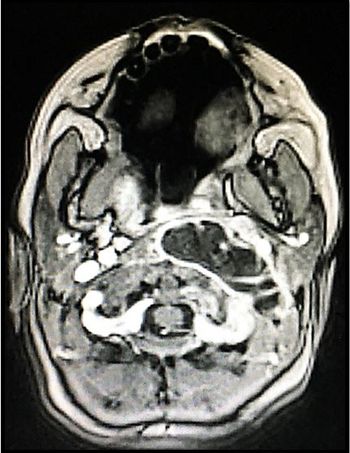

A 34-year-old man with a history of HIV says family members are exaggerating his symptoms but that the headache and double vision are bothersome.